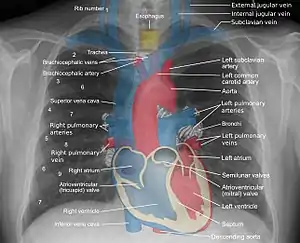

_chest_radiograph_(X-ray).jpg.webp) A normal posteroanterior (PA) chest radiograph of someone without any signs of injury. Dx and Sin stand for "right" and "left" respectively. | |

A chest radiograph, called a chest X-ray (CXR), or chest film, is a projection radiograph of the chest used to diagnose conditions affecting the chest, its contents, and nearby structures. Chest radiographs are the most common film taken in medicine.

Chest radiographs are used to diagnose many conditions involving the chest wall, including its bones, and also structures contained within the thoracic cavity including the lungs, heart, and great vessels. Pneumonia and congestive heart failure are very commonly diagnosed by chest radiograph. Chest radiographs are also used to screen for job-related lung disease in industries such as mining where workers are exposed to dust.[3]

Landmarks

In the average person, the diaphragm should be intersected by the 5th to 7th anterior ribs at the mid-clavicular line, and 9 to 10 posterior ribs should be viewable on a normal PA inspiratory film. An increase in the number of viewable ribs implies hyperinflation, as can occur, for example, with obstructive lung disease or foreign body aspiration. A decrease implies hypoventilation, as can occur with restrictive lung disease, pleural effusions or atelectasis. Underexpansion can also cause interstitial markings due to parenchymal crowding, which can mimic the appearance of interstitial lung disease. Enlargement of the right descending pulmonary artery can indirectly reflect changes of pulmonary hypertension, with a size greater than 16 mm abnormal in men and 15 mm in women.[6]

Appropriate penetration of the film can be assessed by faint visualization of the thoracic spines and lung markings behind the heart. The right diaphragm is usually higher than the left, with the liver being situated beneath it in the abdomen. The minor fissure can sometimes be seen on the right as a thin horizontal line at the level of the fifth or sixth rib. Splaying of the carina can also suggest a tumor or process in the middle mediastinum or enlargement of the left atrium, with a normal angle of approximately 60 degrees. The right paratracheal stripe is also important to assess, as it can reflect a process in the posterior mediastinum, in particular the spine or paraspinal soft tissues; normally it should measure 3 mm or less. The left paratracheal stripe is more variable and only seen in 25% of normal patients on posteroanterior views.[7]

Localization of lesions or inflammatory and infectious processes can be difficult to discern on chest radiograph, but can be inferenced by silhouetting and the hilum overlay sign with adjacent structures. If either hemidiaphragm is blurred, for example, this suggests the lesion to be from the corresponding lower lobe. If the right heart border is blurred, than the pathology is likely in the right middle lobe, though a cavum deformity can also blur the right heard border due to indentation of the adjacent sternum. If the left heart border is blurred, this implies a process at the lingula.[8]